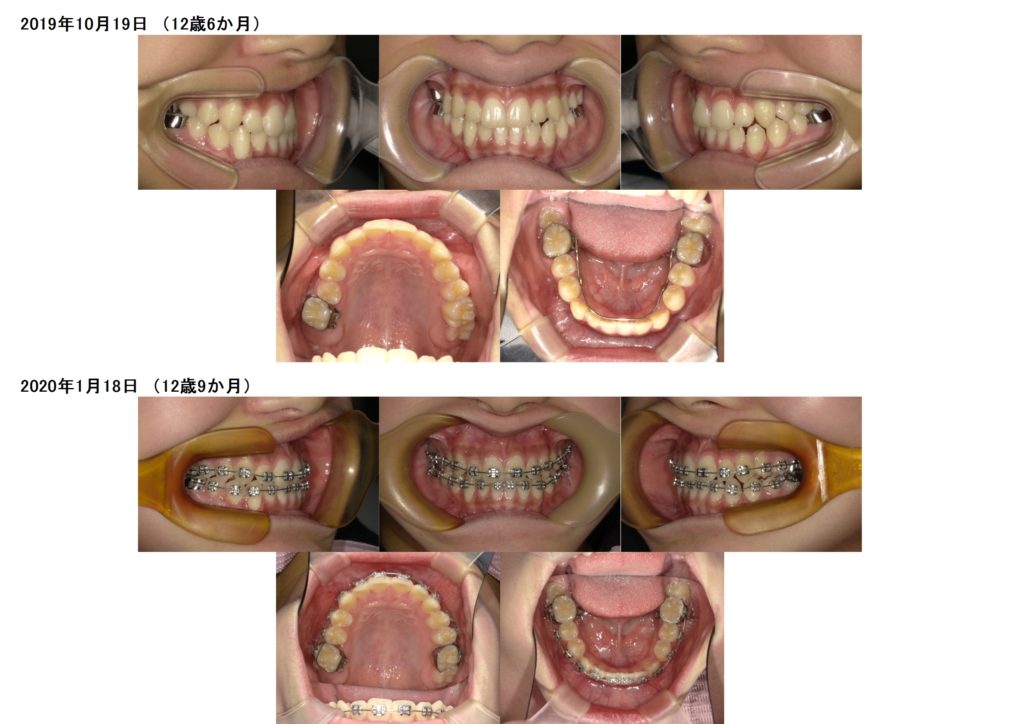

7番目の歯(12歳臼歯)が生え始めたらⅡ期のフルブラケット装置に移行します。

↑上下ブラケット装置をつけました☺

噛み合わせや、歯並びを少しずつ調整していきます。